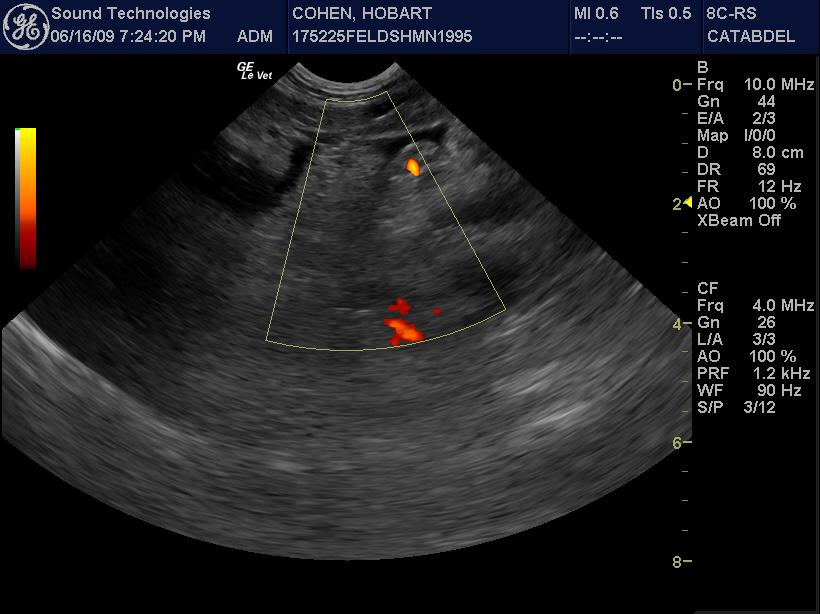

An 8-year-old MN DSH with history of hairballs (currently on Laxatone therapy), was presented for evaluation of vomiting. Abnormalities on physical examination were listlessness and mild dehydration. CBC showed leukocytosis, neutrophilia, basophilia, high MCHC, and elevated MCH. On blood chemistry hyperalbuminemia, elevated ALP and ALT activity, hypercholesterolemia, mild hyperglycemia, slight hypokalemia, and hyperbilirubinemia were evident. Blood gas analysis showed alkalosis with decreased HCO3, PCO2, and TCO2. T-4 was within normal range.

An 8-year-old MN DSH with history of hairballs (currently on Laxatone therapy), was presented for evaluation of vomiting. Abnormalities on physical examination were listlessness and mild dehydration. CBC showed leukocytosis, neutrophilia, basophilia, high MCHC, and elevated MCH. On blood chemistry hyperalbuminemia, elevated ALP and ALT activity, hypercholesterolemia, mild hyperglycemia, slight hypokalemia, and hyperbilirubinemia were evident. Blood gas analysis showed alkalosis with decreased HCO3, PCO2, and TCO2. T-4 was within normal range.

US-guided FNA of the pancreas revealed suppurative pancreatitis

Type of Imaging : Ultrasound